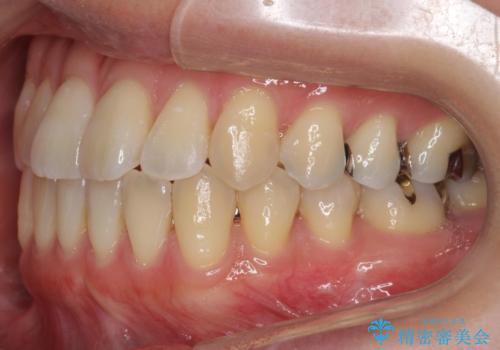

前歯のがたつき 若干受け口 インビザラインで

治療症例の内容

- 前歯のねじれおよび下の前歯が前に出ていることを気にして来院。

インビザラインで治療をおこないました。

前歯のねじれもなおり、比較的短期間でご満足いただけました。

部分矯正コースでしたので左下67の段差は特に治しておりません。

右下567及び左下6の虫歯治療も一緒に行っています。